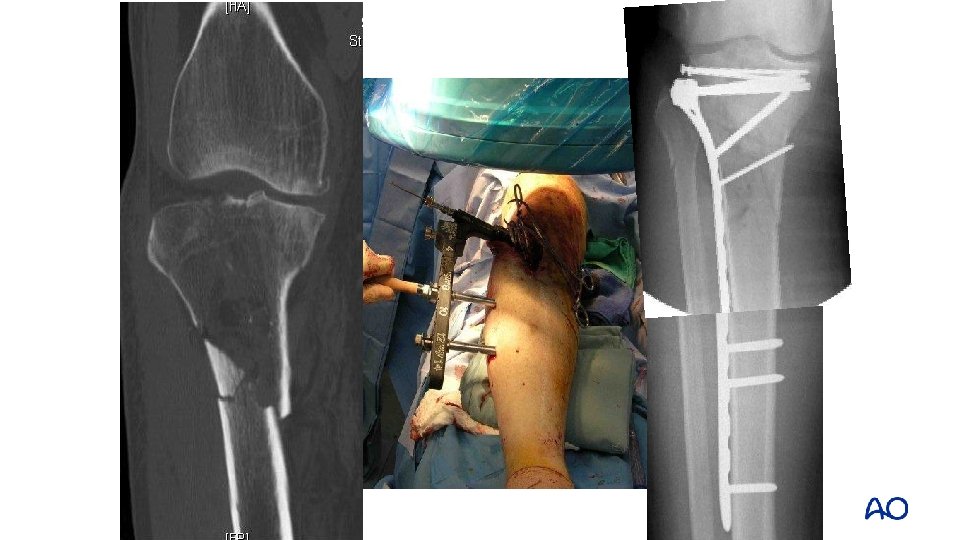

Deformity with distal fractures • Malalignment is common with distal fractures • Vallier: 23% (>40) • Freedman: 8%

Reduction aids for distal fractures • Pointed (percutaneous) clamps • External fixation • Steinman pin • Fibular fixation • Blocking screws

Percutaneous clamps

Clamp + Schanz pin Clam + Ex. Fix

Steinman pin